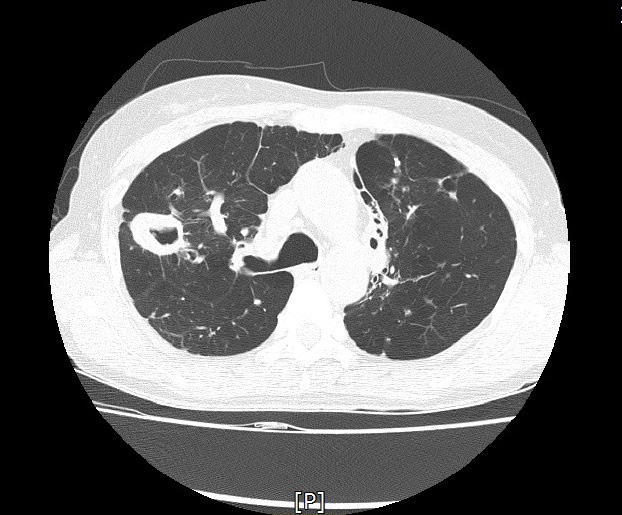

기관지확장증의 CT 사진

논문 한편을 더 살펴 봅시다